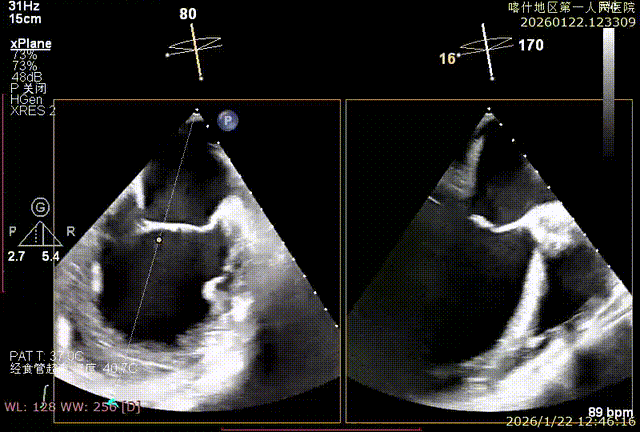

X-plan重度反流

该例患者为VFMR,术前制定手术策略:患者二尖瓣重度反流,后叶严重栓系,心房心室扩大。患者瓣口面积4.5cm2,预计使用两枚XTR解决患者瓣叶脱垂和反流。考虑到先于2区进行钳夹,应该能获得足够的房间隔穿刺高度。术中经不断调整穿刺位点,最终穿刺高度4.4cm。成功穿刺后将第一枚XTR送入二尖瓣正上方,进行弹道测试Orientation调整后,最终定位于2区正上方下左心室。第一枚夹子在左室成功捕捞和钳夹瓣叶后,瓣叶反流程度显著降低,夹子外侧仍见部分反流,随后在第一枚夹子外侧再次放置一枚XTR,瓣叶反流程度进一步降低至微量。通过TEE观察,二尖瓣双孔组织桥稳定,跨瓣压差3mmHg,肺静脉逆流改善明显,手术安全结束。